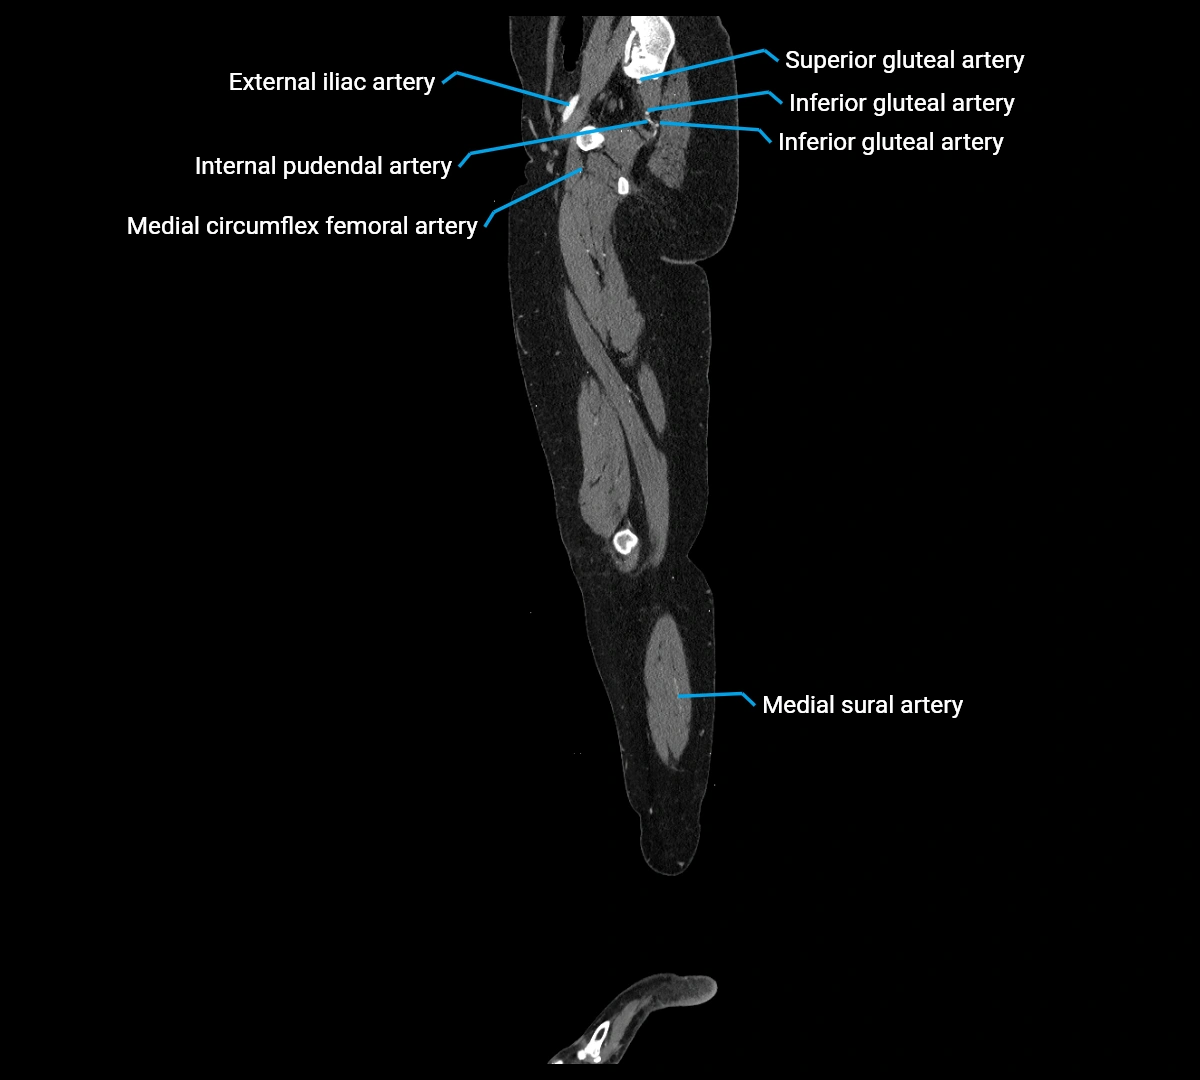

CT images

image